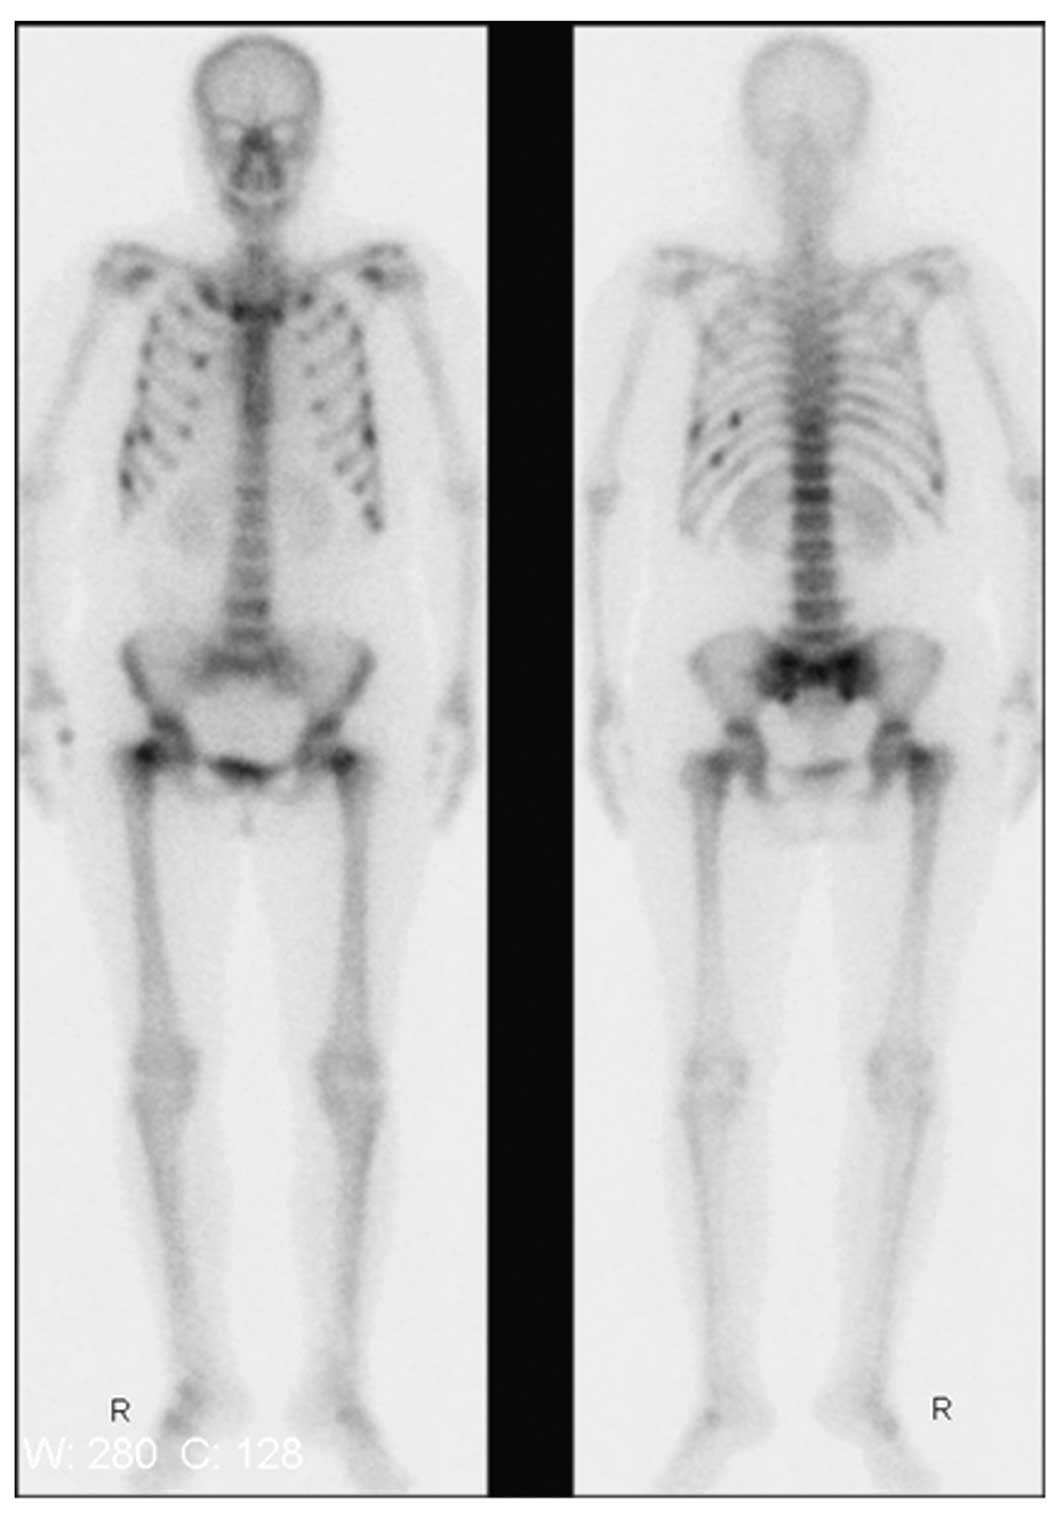

Whole-body bone emission computed tomography (ECT; via the intravenous administration of 99 mTc - MDP) showed that nuclide intake was increased in several locations (Fig. 2), and the cause was considered to be malignant. Whole-body positron-emission tomography CT (PET-CT) examination (Fig. 3) showed that several ribs and double femoral neck (incompletely) had discontinuity and numerous old fracture lines (loose lines) were present, as well as mild T12 compression changes. Local fluorodeoxyglucose (FDG) metabolism increased in the cervical vertebra-2 accessory bone, but did not increase in the regions of reduced local density of the left thyroid gland, which were considered to be thyroid nodules. Bilateral hip joint swelling was accompanied by an increase in FDG metabolism and these regions were classified as inflammatory hip lesions. Bone mineral density tests showed that left forearm bone density had reduced by 17.96% [T-score: −1.43 (−1>T-score >−2.5 is suggestive of bone loss)]. The results of blood phosphorus tests (0.48–0.64 mmol/l) led to the clinical consideration that the patient may be diagnosed with hypophosphatemic osteomalacia. However, re-examination of the patient following the administration of sodium glycerophosphate and Rocaltrol® (Roche, Shanghai, China) demonstrated that the treatment was ineffective (the blood phosphorus concentration did not increase). Tests of blood from the right subclavian vein indicated that the concentration of fibroblast growth factor (FGF)-23 was 32.44 ng/l (normal, 40–90 ng/l).

Figure 2

Whole-body bone imaging emission computed tomography. Whole-body positron-emission tomography CT (PET-CT) examination showed that several ribs and double femoral neck (incompletely) had discontinuity and numerous old fracture lines (loose lines) were present, in addition to mild T12 compression changes. Bilateral hip joint swelling was accompanied by an increase in FDG metabolism and these regions were classified as inflammatory hip lesions.